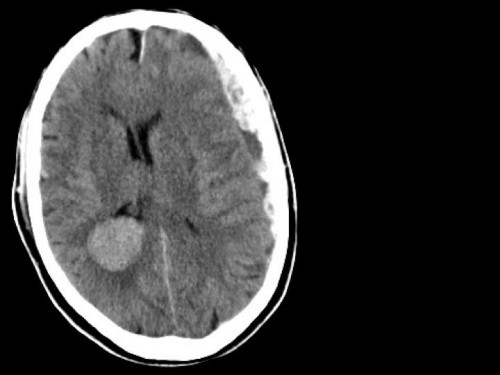

70-jähriger passionierter Radfahrer. Bislang war er nie ernsthaft erkrankt. Er ist mit dem Rad auf seiner Tour von Rostock nach Garmisch alleine unterwegs, als er unbehelmt auf nasser Straße stürzt.

Der Patient wird deutlich vigilanzgemindert (Glasgow-Coma-Score 10) über den Schock-OP eingeliefert.